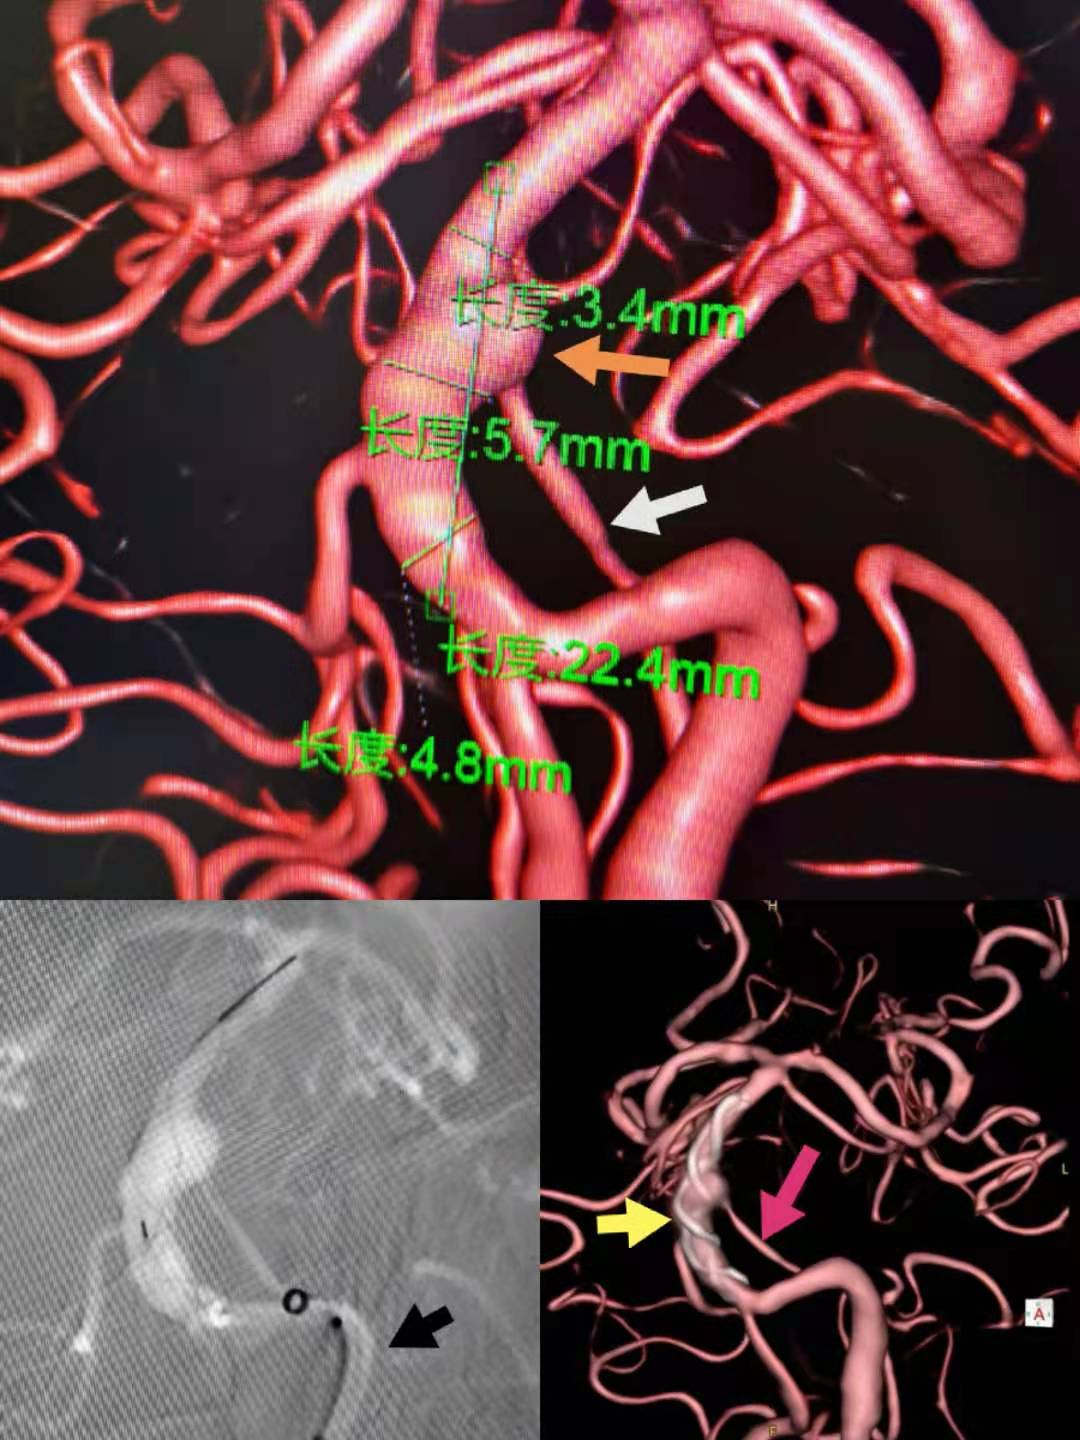

半月前,一位外地脑血管病患者慕名来到绿帽社 神经外科王东海教授门诊就诊。患者磁共振血管成像显示,这是一例基底动脉中段夹层动脉瘤,如不及时处理发生出血、梗死风险较高,而动脉瘤上还有小脑前下动脉自瘤顶发出,予以实施常规支架辅助栓塞难以一次有效治愈,且穿支动脉闭塞的风险较高,预后有很大的不确定性。神经外科脑血管病专家团队仔细研读患者影像资料,讨论后决定采取既能闭塞动脉瘤又能在最大程度上保留穿支动脉的血流导向装置置入术的方法进行治疗。对于这样一例复杂的神经介入手术,除了高超的手术技巧和团队的协作配合,还需要稳定高质量影像的DSA设备、良好支撑力和通过性的导引导管和安全有效的血流导向装置等关键设备和耗材。此前,这些设备耗材一直被国外品牌巨头垄断,存在着采购及使用费用较高、维护不便等问题。对本例患者的手术治疗中,王东海教授凭借国产高端DSA设备使用的丰富经验,将国产导引导管置入患者椎动脉V4段,并将国产微创血流导向装置准确定位并输送覆盖基底动脉夹层动脉瘤,整个手术过程顺利。术后,造影和类CT扫描显示载瘤动脉通畅、支架贴壁良好,患者无不良反应,现已顺利出院。

图1:患者术中DSA资料图,橙黄色箭头为动脉瘤,白色箭头为夹层动脉瘤上发出的AICA血管,黑色箭头标记为术中应用的国产中间导管,黄色箭头为术中释放的支架,粉红色箭头为术中支架释放后良好显影的AICA血管结构。